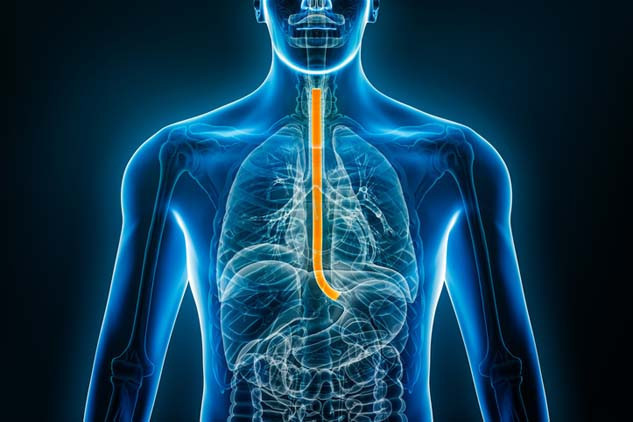

Bu başarı, Andrew’un artık ameliyat edilebileceği anlamına geliyordu; ‘özofajektomi’ yapılacaktı yani sağ akciğeri söndürülecek ve yemek borusunun yaklaşık 15 santimetrelik kısmı kesilip atılacaktı.

Tüm bu acıların ardından altı ay sonra doktor inanılmaz bir haber verdi: Tümör o kadar küçülmüştü ki lenf düğümlerinde neredeyse ölçülemez hale gelmişti. Yemek borusundaki tümör ise bir elma boyutundan ceviz boyutuna gerilemişti.